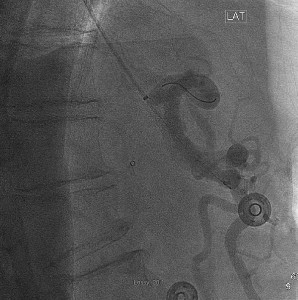

Following treatment of restenosis, there was rapid flow of contrast into the splenic and common hepatic arteries (Fig 3).

Selective injection of the celiac artery showing a patent proximal stent post-angioplasty. The wire tip is visible in the splenic artery in this lateral projection.